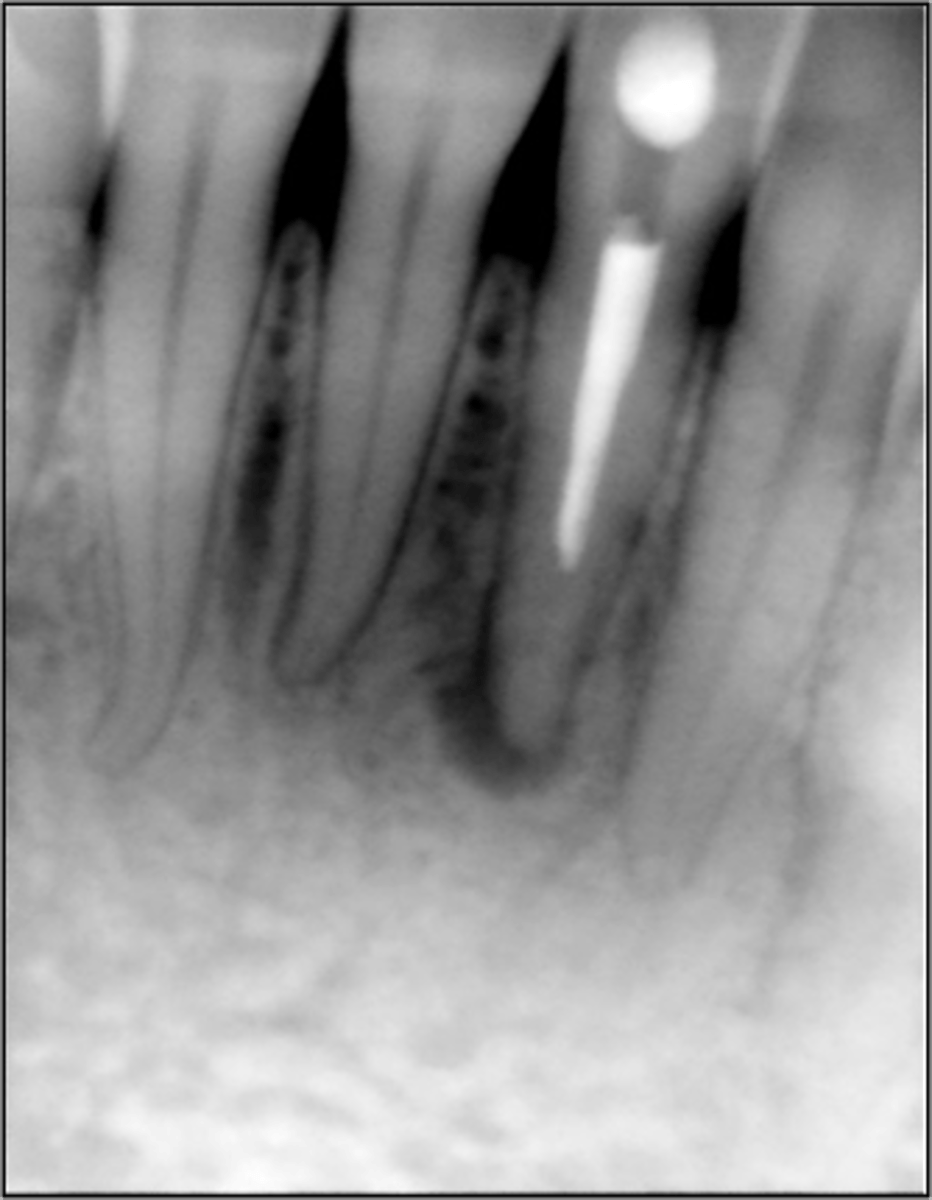

Check if missed MB2

RCT 10 years ago thru bridge

Sinus tract 3 years ago...apicoectomy done

Sinus tract returned.

What do we do?